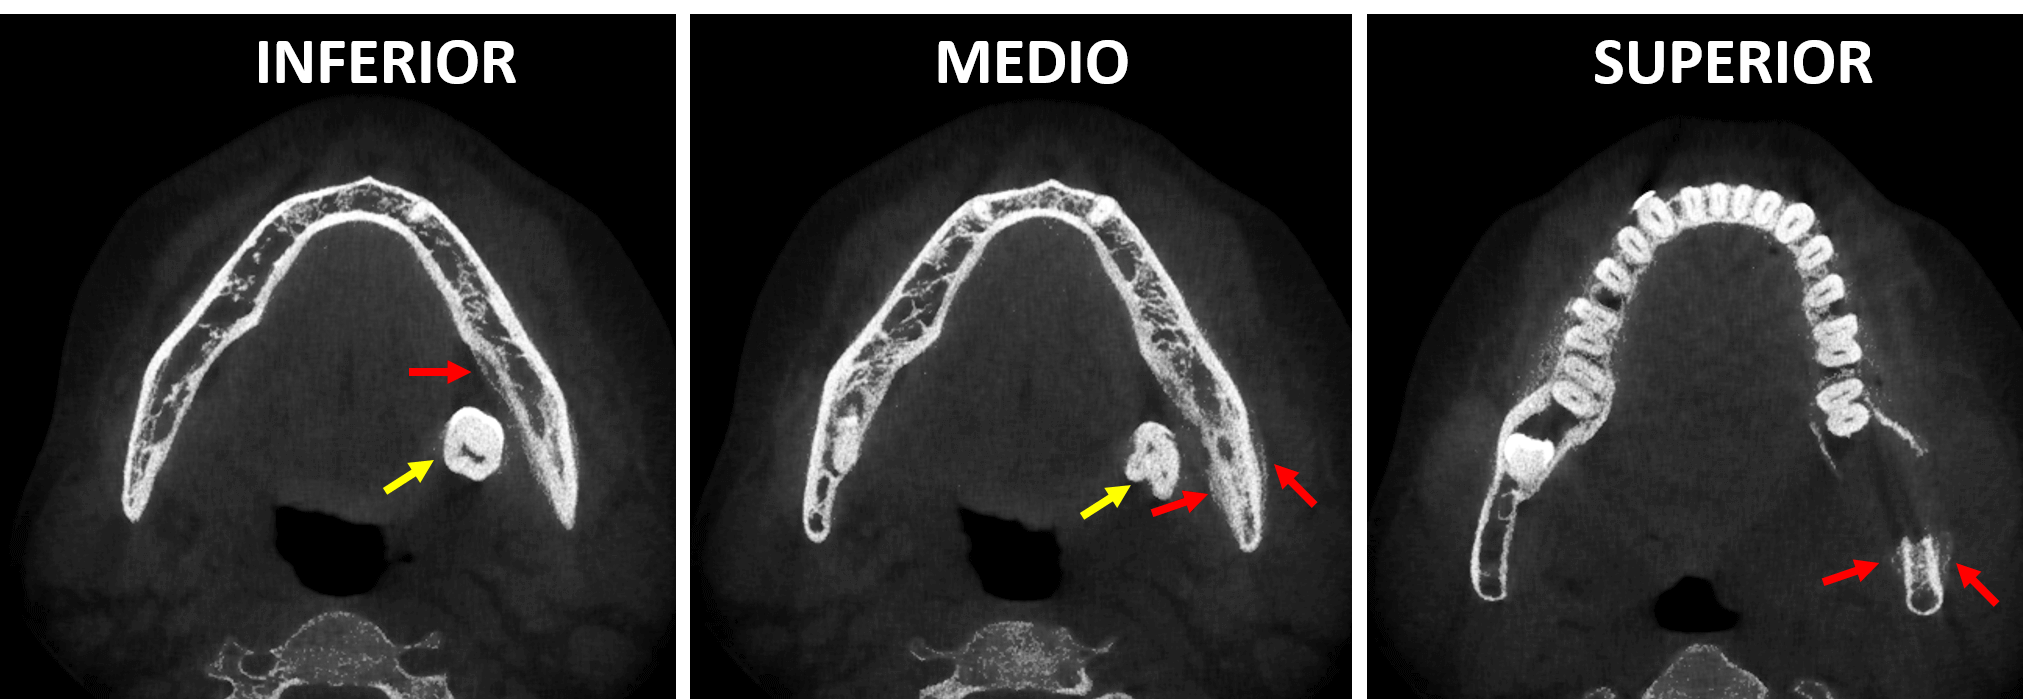

En cortes transaxiales (Fig.2) y en cortes axiales (Fig.3) se observa el órgano dentario 38 localizado por lingual en el tejido blando adyacente al cuerpo mandibular (flechas amarillas), donde se observa también la ausencia de la tabla ósea lingual, asi como la ausencia parcial de la tabla ósea externa en relación con una imagen hipodensa amplia sugerente de un lecho quirúrgico que compromete también el cortical superior del conducto dentario inferior. Nótese las tenues imágenes hiperdensas dependientes de la tabla externa e interna (flechas rojas) sugerentes de una neoformación ósea compatible con una reacción perióstica.